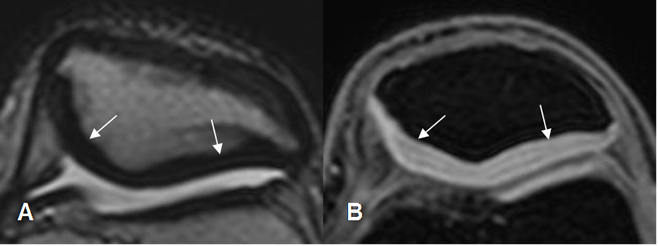

La patela es estabilizada por múltiples estructuras. En la parte superior por el tendón del cuadriceps, en la inferior por el tendón patelar, en la parte interna por el retináculo medial y vasto interno y en la externa, por el retináculo lateral, el vasto externo y la banda iliotibial. Los retináculo son estructuras hipointensas, que se insertan en los bordes de la patela y el fémur. (12). (Fig 33).

Fig 33. Retináculos normales.

A: RM axial 3D STIR en T1 y B: RM axial en T1. Retináculos normales hipointensos, entre la patelay el fémur. Medial (Flechas gruesas) y lateral (Flechas delgadas).